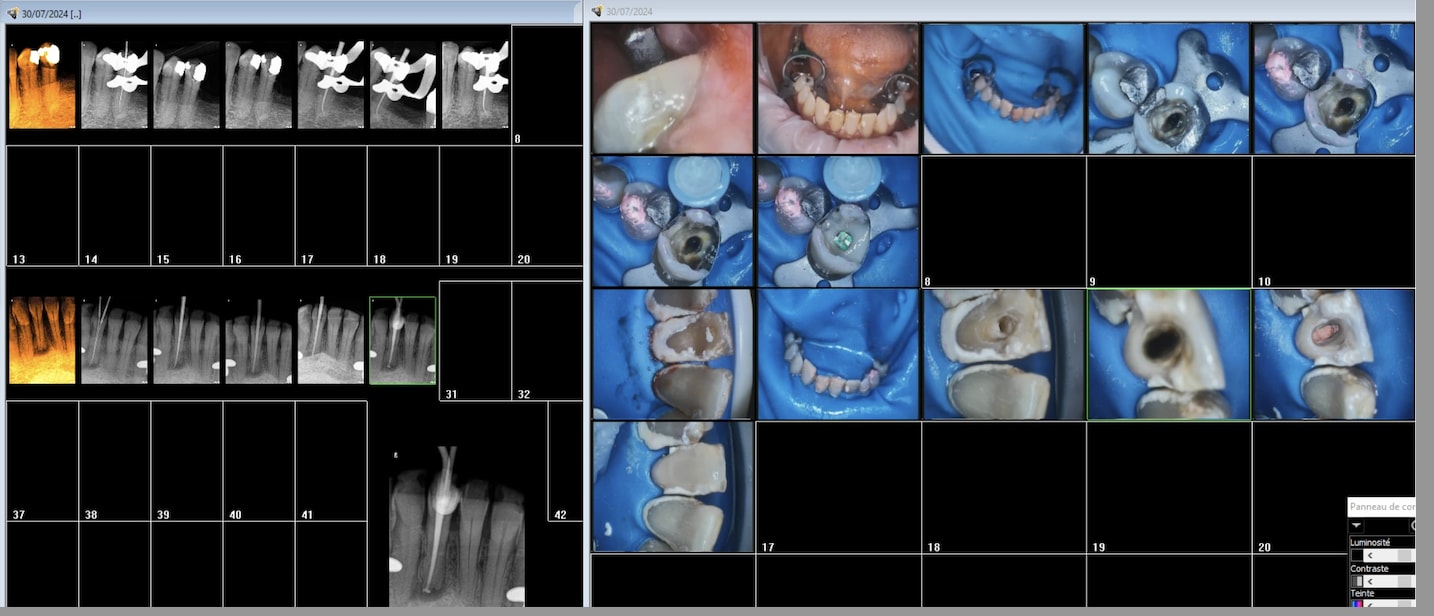

Classe 5 sur une 7 dans la joue sans digue.

Y37p03iis7hfgmk3e6wr63nip64x - Eugenol

Des fois je m'amuse aussi avec la digue mais pour 30 balles et quelques c'est pas tous les jours. En général c'est optragate et linguafix.

Z632mcmk2tsr4qkdp0f4p9sddtte - Eugenol

Vhehprmt8vy2bea0d70jxlcdqrgg - Eugenol

Et7jtaj0pdi18gzjlxjiamlx15gs - Eugenol